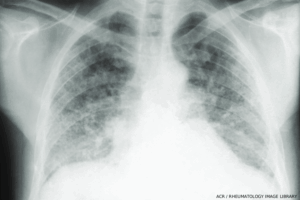

Bilateral interstitial fibrosis involving the lower two-thirds of the lung fields is common in systemic sclerosis. In the lower lung fields are “honeycomb” changes. The heart is not enlarged. (Click to enlarge.)